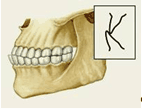

Различают несколько вариантов нормального П. (ортогнатический, прогенический, прямой, бипрогнатический). Они характеризуются смыканием зубных рядов на всем протяжении и отличаются друг от друга лишь особенностями смыкания функционально ориентированных групп зубов, в частности передних. Эталонным принято считать ортогнатический прикус (рис. 5, а), при котором верхний зубной ряд на всем протяжении перекрывает нижний, а во фронтальном участке верхние резцы перекрывают нижние не более чем на 1 /3 коронковой части зуба; между резцами верхней и нижней челюстей имеется режуще-бугорковый контакт. Прогенический прикус (рис. 5, б) отличается умеренным выстоянием нижнего зубного ряда. Прямой прикус (рис. 5, в) характеризуется тем, что верхние резцы не перекрывают нижние, а смыкаются режущими краями. При бипрогнатическом прикусе (рис. 5, г) верхние и нижние резцы наклонены в сторону преддверия рта, но между ними сохранен режуще-бугорковый контакт. Для всех вариантов нормального прикуса обязательным условием является нормальное функционирование зубочелюстной системы.

Рис. 5а). Схематическое изображение челюстей при основных разновидностях нормального прикуса (вид сбоку): ортогнатический прикус.

Рис. 5б). Схематическое изображение челюстей при основных разновидностях нормального прикуса (вид сбоку): прогенический прикус.

Рис. 5в). Схематическое изображение челюстей при основных разновидностях нормального прикуса (вид сбоку): прямой прикус.

Рис. 5г). Схематическое изображение челюстей при основных разновидностях нормального прикуса (вид сбоку): бипрогнатический прикус.